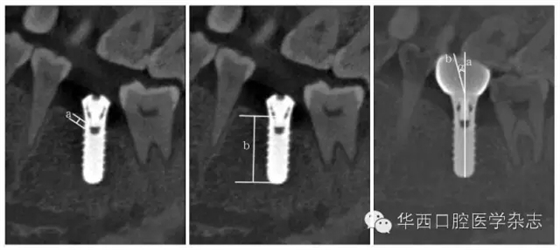

分別拍攝患者種植術(shù)后1周、種植術(shù)后3個(gè)月(同期行冠修復(fù))、修復(fù)后3個(gè)月、修復(fù)后12個(gè)月共4個(gè)時(shí)間點(diǎn)錐形束CT(cone beam computed tomography,CBCT)圖像。利用One Volume Viewer軟件的長(zhǎng)度測(cè)量工具進(jìn)行測(cè)量,測(cè)量基準(zhǔn)線由種植體矢狀剖面截圖最中間的一張確定。依據(jù)參考文獻(xiàn)[5-6]的測(cè)量方法,分別測(cè)量不同時(shí)間點(diǎn)CBT、BH、CA(如牙冠長(zhǎng)軸相對(duì)于種植體長(zhǎng)軸偏向近中,CA為正值;如其偏向遠(yuǎn)中,CA則為負(fù)值)。各指標(biāo)測(cè)量方法如圖1所示。

左:a為CBT;中:b為BH;右:a為種植體長(zhǎng)軸,b為牙冠長(zhǎng)軸,α為CA。

圖1 CBT、BH和CA的測(cè)量方法